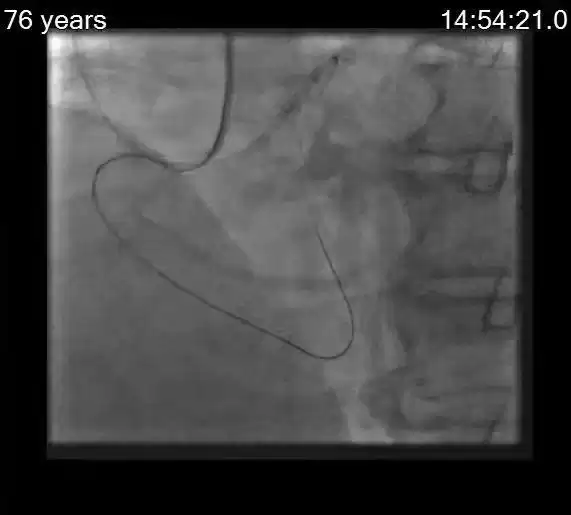

术中实况:技术熔炉

术后:生命通道重燃